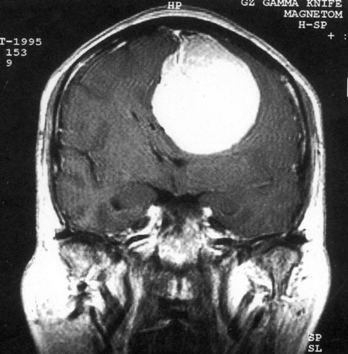

问题 病历摘要:??患者女性,37岁。大便时突起炸裂样头痛3小时,伴喷射样呕吐。既往体健。体检:T37.5℃,BP145/90mmHg,R20次/分,P85次/分。神志清楚,颅神经检查无异常,颈强直,克、布氏征(-),四肢肌力、肌张力正常,病理征(-)。 动脉瘤术中出血时,可采取哪些措施?提示:入院后第?2日患者行右翼点开颅瘤颈夹闭术,术中分离瘤颈时,动脉瘤破裂。